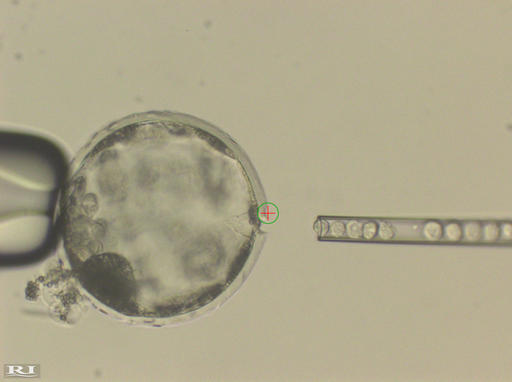

Scientists used human stem cells, which are capable of producing a wide variety of specialized cells. They injected pig embryos made in the lab with three to 10 of those cells apiece, and implanted the embryos into sows. At three to four weeks of development, 186 embryos were removed and examined.